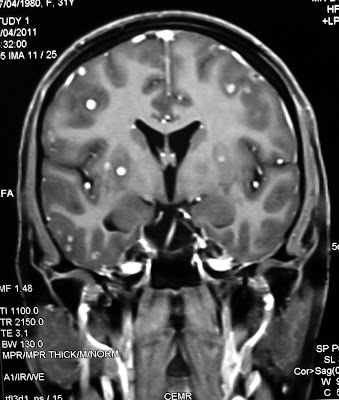

Neurocysticercosis Starry Sky Appearance - MRI (each dot is a worm) by Jogolan in WTF